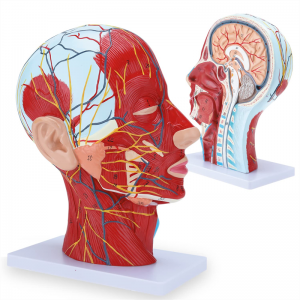

| פֿעיִקייטן | דער מאָדעל ווייזט די היגע מאָרפאַלאַדזשי פון די ינער און ויסווייניקסט זייטן פון די מידיאַן סאַגיטטאַל אָפּטיילונג פון די קאָפּ און האַלדז, און די סטראַקטשערז פון בלוט כלים און נערוועס און עס זענען 84 פּאַרץ ינדאַקייטינג וואונדער אין גאַנץ. |

【1: 1 לייווז】 מידיאַן אָפּטיילונג פון 1: 1 נאַטירלעך גרויס קאָפּ & האַלדז אויבנאויפיקער נעוראַל וואַסקיאַלער מוסקל מאָדעל (רעכט זייַט). פייַן ווערקמאַנשיפּ. פאָרשלאָגן אַ פול קייט פון אַנאַטאַמיקאַל פֿעיִקייטן.

【Superficial Neurovascular Muscle Model】Highly detailed, numbers marked, detachable ear, deepen the understanding of the superficial muscles, vessels, nerves and the internal structures of the head & neck. רויט-אַרטעריע, בלוי-אָדער, געל-נערוו.

【פֿעיִקייטן】 עס געוויזן די אויבנאויפיקער מאַסאַלז פון די יקספּאָוזד פּנים; די אויבנאויפיקער בלוט כלים & נערוועס פון די פּנים & סקאַלפּ; די ינער סטראַקטשערז פון פּאַראָטיד דריז & אויבערשטער רעספּעראַטאָרי שעטעך; די סאַגיטטאַל קרייַז-אָפּטיילונג סטרוקטור פון די סערוואַקאַל רוקנביין.

דער מאָדעל ווייַזן דעטאַילס פון די רעכט קאָפּ האַלדז און מיטן סאַגיטטאַל אָפּטיילונג פון דער מענטש. אַרייַנגערעכנט די אויבנאויפיקער

מאַסאַלז פון די יקספּאָוזד פּנים; די אויבנאויפיקער בלוט כלים און נערוועס פון די פּנים און סקאַלפּ; די ינער סטראַקטשערז

פון פּאַראָטיל דריז און אויבערשטער רעספּעראַטאָרי שעטעך; די סאַגיטטאַל קרייַז-אָפּטיילונג סטרוקטור פון די סערוואַקאַל רוקנביין.

דער מאָדעל איז נאַטירלעך גרויס קאָפּ און האַלדז אויבנאויפיקער נעוראָוואַסקולאַר מוסקל מאָדעל, 1 קאָמפּאָנענט, ווייַזונג די דעטאַילס פון די מענטשלעך רעכט קאָפּ און מעדיאַן סאַגיטטאַלע אָפּטיילונג, אַרייַנגערעכנט די יקספּאָוזד בעשאָלעם און די מעדיאַל סטרוקטור פון די פּאַראָטיד דריז און אויבערשטער רעספּעראַטאָרי שעטעך, און די סאַגיטטאַל אָפּטיילונג סטרוקטור פון די סערוואַקאַל רוקנביין